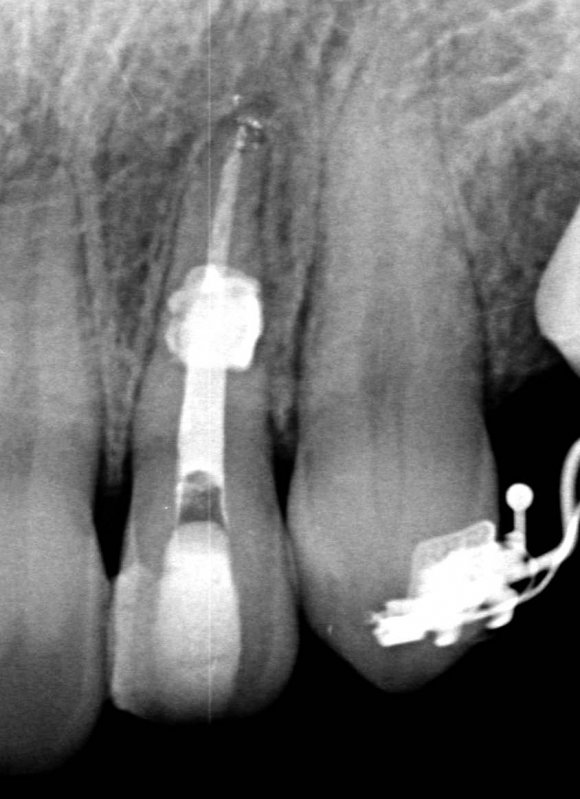

Also, there were signs in favor of internal resorption. The defect was below the cervical part, which is not typical of external cervical resorption. The response to cold stimuli reduced, which is not characteristic of external resorption, as it affects the pulp only in the last stages of tooth structures decay. Furthermore, the X-ray obliteration of the root canal beyond the resorption area is not characteristic of external resorption. Visit 1: Pre-op X-ray plus anesthesia with sol. Ubisthesini 4% -1 ml, isolation with rubberdam. The access was made as close as possible to the incisal edge. When opened, at first glance the pulp chamber looked quite II.

The patient started orthodontic treatment, however, tooth 2.2 was temporarily not included in the orthodontic therapy at the endodontist's request, who was willing to observe it for a year. Furthermore, increased resorption could have been provoked. As of today, the tooth is included in the orthodontic treatment and is being followed up.

In eighteen-month time, the stabilized process is observed, meaning that the diagnosis has been correct and the manual work has been performed without problems. No complaints are observed.